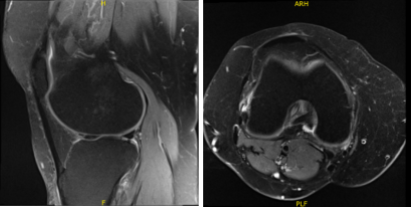

The patient presented an MRI result that showed undersurface tear of the medial meniscal body resulting in a small peripheral meniscal flap. Small radial tear at the free edge of the lateral meniscal body. Mild to moderate cartilage loss in the medial compartment and a small joint effusion.

MRI-3T Knee non-contrast